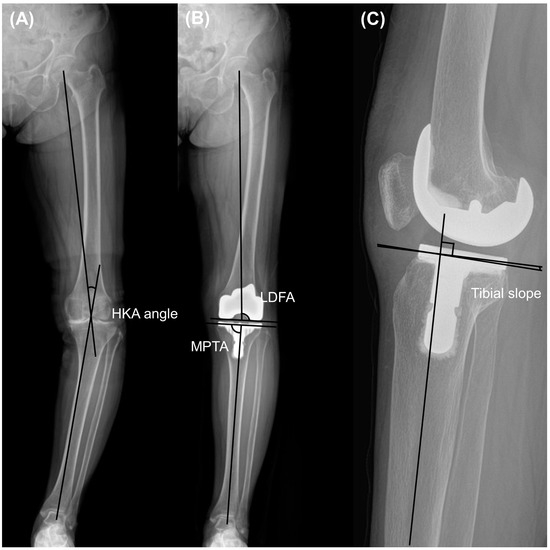

The radiographs obtained before and two years after the surgery were analyzed. The analysis involved measuring the Hip-Knee-Ankle (HKA) angle, which is the angle formed between the line connecting the center of the femoral head to the center of the knee and the line from the center of the knee to the center of the talus, using whole-leg standing radiographs. Varus and valgus were designated as positive and negative HKA angles, respectively [16]. Additionally, the lateral distal femoral angle (LDFA) and medial proximal tibial angle (MPTA) were assessed to examine the preoperative phenotype and implant position in the coronal plane [17,18]. The LDFA was defined as the angle between the line parallel to the femoral condyle and the mechanical axis of the femur. The MPTA was defined as the angle between the line parallel to the tibial plateau or component and the anatomical axis of the tibia (Figure 1). Knee preoperative phenotypes were classified as previous investigation [19]. Alignment variation was defined as a 3° range for any of these angles. The mean values of these phenotypes represented 3° increments in the angle, starting from the overall mean value observed in a young non-osteoarthritic population (NEUHKA0° = 0°, NEULDFA0° = 87°, NEUMPTA0° = 87°). The nomenclature of the phenotypes was constructed as follows: the first part (NEU, VAR, and VAL) indicated the alignment direction; the second subscripted part (HKA, LDFA, and MPTA) represented the measured angle, and the last part (0°, 3°, 6°, etc.) indicated the mean deviation of the phenotype from the mean value. Postoperative HKA angle outliers were defined as greater than 3° or less than −3°, and LDFA or MPTA outliers were defined as greater than 93° or less than 87°, as described in a previous study [20]. The distribution rates of the HKA, LDFA, and MPTA phenotypes were compared between the two groups. Correlation analysis was performed for the preoperative HKA angle and other pre- and postoperative variables, including LDFA, MPTA, tibial slope, femoral condylar offset, joint line distance, and femoral component rotation angle. The tibial slope was quantified as the angle formed between the mid-diaphysis line of the tibia and the line representing the posterior inclination of the tibial plateau or implant in the lateral view.

Figure 1.

Measurement included (A) hip-knee ankle (HKA) angle, (B) lateral distal femoral angle (LDFA) and medial proximal tibial angle (MPTA) on whole-leg standing radiographs, and (C) tibial slope on lateral view radiographs.